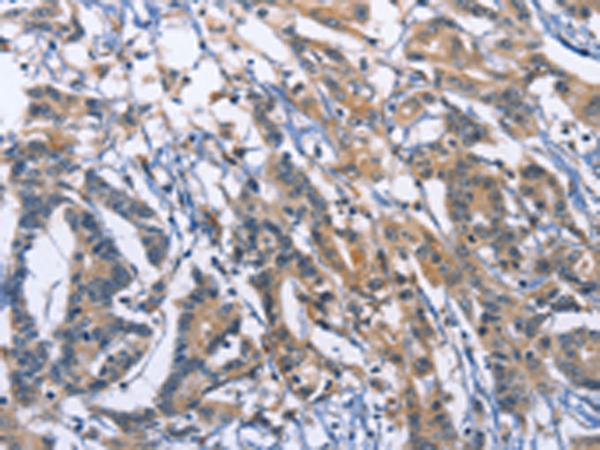

分类: 科研抗体货号: P00648别名: PHD3; HIFPH3; HIFP4H3应用: IHC反应种属: Human, Mouse, Rat